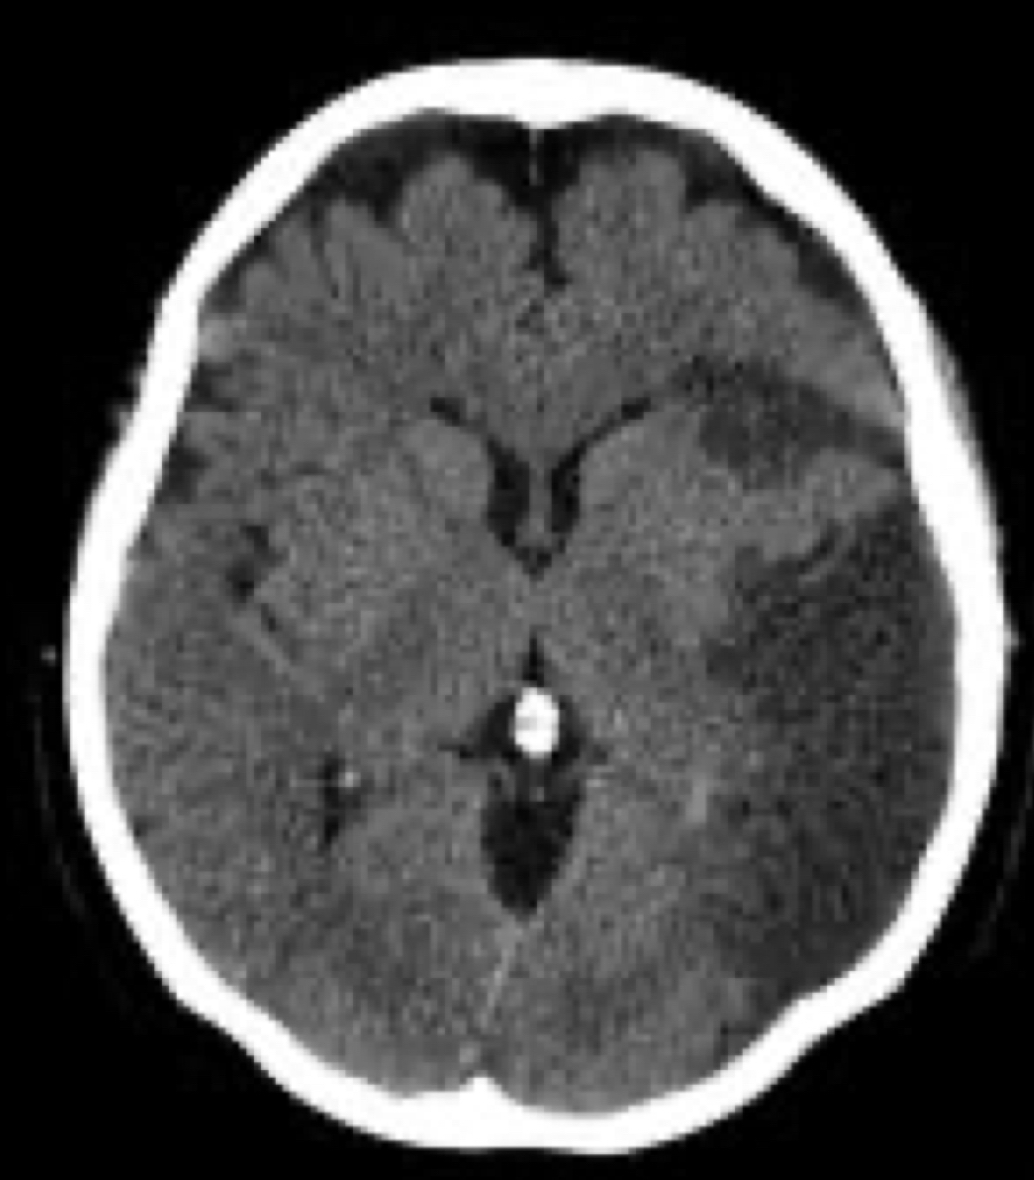

9

Q

¿Que es?

A

EVC isquemico crónico